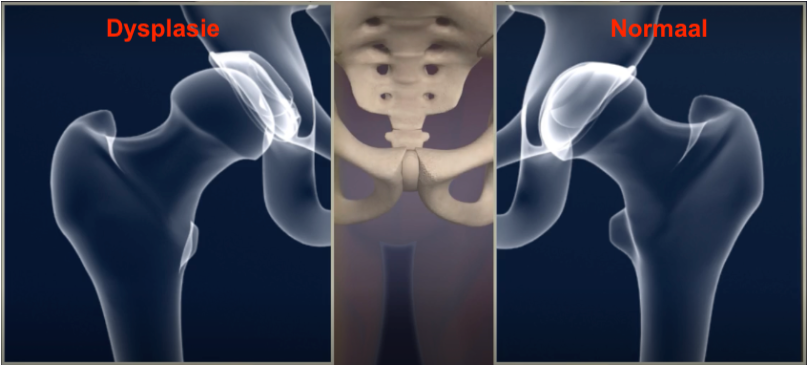

Heupdysplasie of D.D.H. (developmental dysplasia of the hip) is een ontwikkelingsstoornis waarbij het heupgewricht niet goed gevormd is.

De afwijking kan zich zowel ter hoogte van de heupkom als ter hoogte van de heupkop situeren. De kom kan te ondiep zijn, slecht georiënteerd, te steil of zelfs misvormd zijn.

Ter hoogte van de heupkop manifesteert dysplasie zich door een te steile nek die dan meestal ook te veel naar voren gericht is. Bovendien kan er een eventuele misvorming en afplatting van de kop aanwezig zijn.

1) Een onvoldoende overdekking van de heupkop door een te kleine heupkom.

2) De heupkom staat in een slechte en te steile positie.